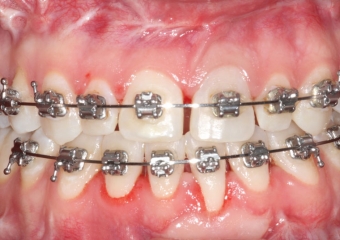

Mordida inicial - Clínica Cliniface

Mordida inicial